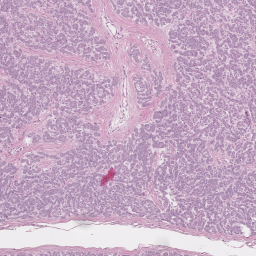

CATCH Dataset. We further use the publicly available Pan-tumor CAnine CuTaneous Cancer Histology dataset (CATCH) by Wilm et al. [25]. With 350 WSIs from 282 individual canine patients, the H&E-stained tissue slides were digitized using Leica ScanScope CS2 linear scanners, at a resolution of 0.25μm0.25𝜇𝑚0.25\,\mu m per pixel. In this dataset, seven different tumor types are included, with 50 WSIs each. Annotation of tissue segmentation maps was performed by a pathologist, as well as three medical students under a pathologist supervision. We consider all tumor subtypes as a combined tumor class and the rest of the areas as a background class. Using 42, 21, and 7 WSI, equally distributed between known tumor types for training. The remaining WSIs are considered as style source, with patient-wise style variations being assumed the most relevant variation.

Refer to captionRefer to captionRefer to captionRefer to captionRefer to captionRefer to captionRefer to captionRefer to captionRefer to captionRefer to captionRefer to captionRefer to captionRefer to captionRefer to captionRefer to captionRefer to captionRefer to captionRefer to captionRefer to captionRefer to captionRefer to captionRefer to captionRefer to captionRefer to captionRefer to captionRefer to captionRefer to captionRefer to captionRefer to captionRefer to captionRefer to captionRefer to captionRefer to captionRefer to captionRefer to captionRefer to captionRefer to captionRefer to captionRefer to captionRefer to captionRefer to captionRefer to captionRefer to captionRefer to captionRefer to captionRefer to captionRefer to captionRefer to captionRefer to captionRefer to captionRefer to captionStyle Transfer [6]Ours (Nearby Style Cond.)Ours (Multi-Patch Style Cond.)StylesStylesStyles (selection, 3 of 10)LayoutsLayoutsLayouts

Figures 4 and 5 show examples of generated images for the HER2 and CATCH dataset. The style transfer baseline [6] captures some of the staining characteristics for the HER2 dataset, but also creates some darker blurred areas, which are not commonly seen in HER2 images. On the CATCH dataset, the global color scheme is transferred to the synthetic images, but no delineation between tumor and background area is visible. For our method the generated images adhere to the spatial layout and also represent the styles in the query images for both the nearby and multi-patch configuration, even though the query images were not seen during training.